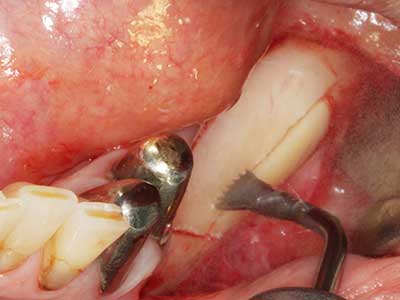

Piezosurgery has additional advantages when harvesting bone blocks. In addition to the high precision with osteotomy described above, the use of the thin saw tips specifically minimizes loss of material. Greater loss of material during harvesting can be expected with the thicker instrument tips, particularly when using Lindemann drills (Lakshmiganthan, Gokulanathan et al. 2012). The basal separation, which is necessary particularly for retromolar block transplants, is simplified by specially designed rectangular saws, with the result that piezosurgery is viewed as a precise, simple and safe procedure for harvesting retromolar bone blocks (Happe 2007) (Fig. 1-12).